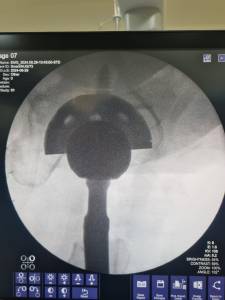

A young man with previous history of Panner’s disease presented at our clinic. The patient experienced a locking sensation in his elbow during movement. No obvious deformity such as an osteochondrosis was observed via X-ray imaging. However, during clinical examination, the orthopaedic team noted a disturbance during movement in the joint. After consideration of the patient’s history, we decided to perform a surgical exploration, during which the osteochondral fragment was successfully identified and removed. Panner’s disease, which refers to osteochondrosis of the capitellum of the humerus, is observed in children between ages 4 to 10, and is typically self-limiting. In this particular individual, the disease was not resolved; instead, the osteochondrosis remained loose in the joint, creating a locking sensation in the joint during movement.